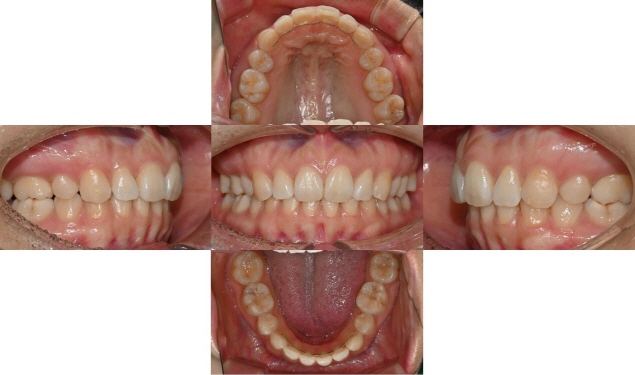

2025.5.20 교정치료 완료

과개교합 치료 전후 사진 비교

총 3달 정도의 치료기간 동안 오른쪽 틀어진 앞니가 가지런하게 배열되었고 치아사이 공간도 타이트하게 닫을 수 있었습니다. 또한 위아래 앞니가 서로 세게 닿지 않도록 위 앞니를 위로 살짝 올려주어 과개교합을 개선하였습니다.

과개교합의 경우 일반 교정장치로 부분교정하기에는 쉽지 않은 치료과정이나, 인비절라인의 경우 부분교정으로도 어느 정도의 과개교합의 개선은 충분히 가능합니다. 치료 마무리 후 송곳니까지 고정식 유지장치를 붙이고 가철식 유지장치를 제작하여 다시 틀어지거나 벌어지지 않도록 하였습니다.